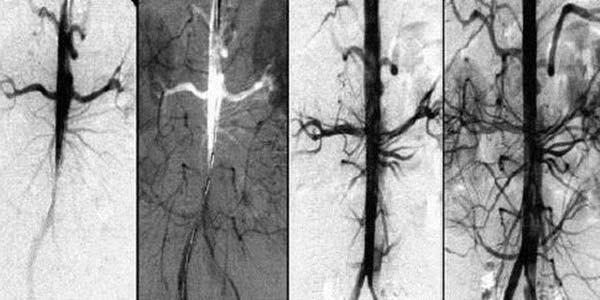

Asinsvadi un hipertensija

Asinsvadu bojājumi un aterosklerozi

Augsts spiediens ievainoja asinsvadu sieniņas, veicinot aterosklerozi un trombu veidošanos visā organismā:

• Asinsvadu sieniņu sacietēšana un sašaurināšanās

• Nieru bojājumi un hroniska mazspēja

• Redzes pasliktināšanās — tīklenes bojājumi

• Paaugstināts insulta risks par 7 reizēm